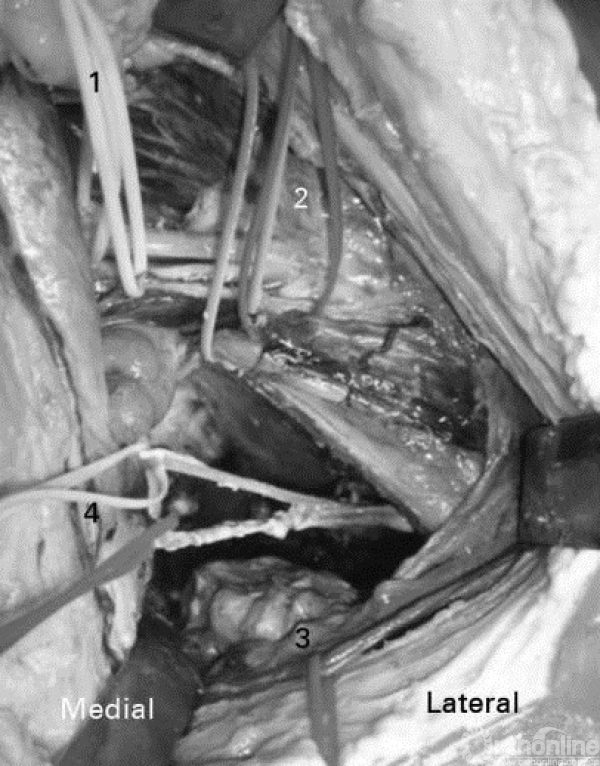

3、内部显露

1)腹股沟神经;

2)股外侧皮神经;

3)股神经和生殖神经分支;

4)髂外动脉/静脉;

5)髂前上棘(ASIS);

6)髂腰肌;

7)髋臼顶;

8)腹壁下血管;

9)死亡之冠;

10)闭孔神经血管;

11)闭孔内肌肌肉;

12)输精管;

13)闭孔神经。

1)生殖股神经分支和股外侧皮神经;

2)髂外动脉和静脉;

3)腹壁下血管;

4)闭孔神经和血管。